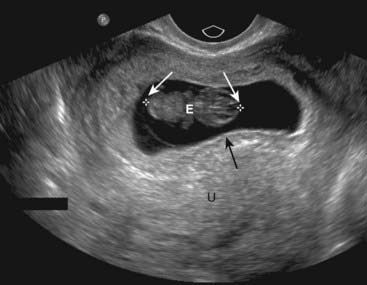

Figure 19-26 Early intrauterine pregnancy.

There is a single live intrauterine pregnancy (solid white arrows) contained within the gestational sac (solid black arrow) inside the uterus (U). Using a measurement called the crown-rump length, (between the white arrows) the embryo (E) was estimated at 9 weeks of age. Sonographic gestational age begins on the first day of the last normal menstrual cycle because, for most individuals, that is a more certain date than the actual date of ovulation.

image Conversely, the demonstration of a live embryo outside of the uterus is diagnostic of an ectopic pregnancy. This is not a common occurrence with most ectopic pregnancies (Fig. 19-27).

Figure 19-27 Ectopic pregnancy.

A, A normal endometrial stripe (solid black arrow) is present with no evidence of a pregnancy in the uterus (U). B, There is an adnexal mass (solid white arrow) containing an embryo (E). There is fluid in the cul-de-sac (C). The demonstration of an embryo outside of the uterus is diagnostic of an ectopic pregnancy.